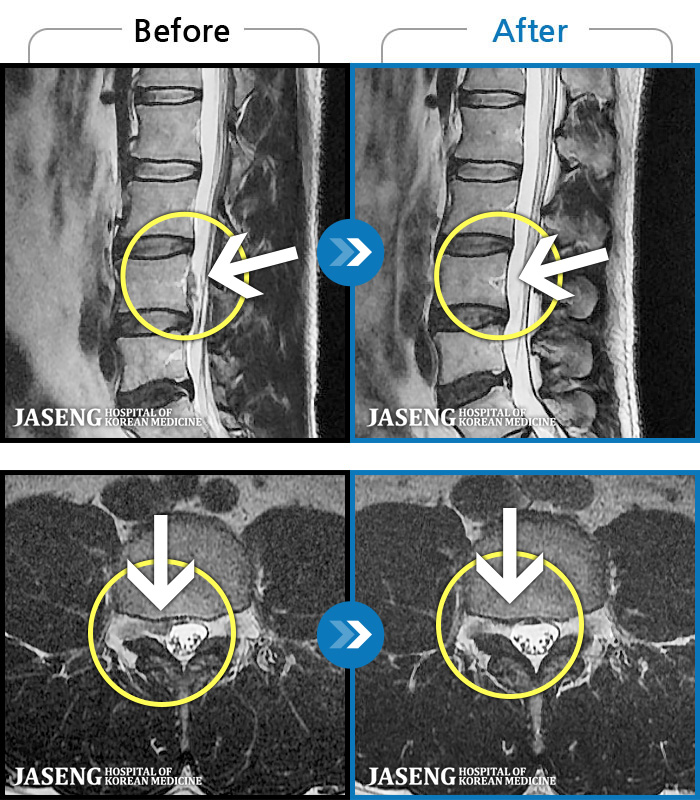

Before

After

환자에게 사전 동의를 받아 동일 조건에서 촬영되었습니다.

개인에 따라 치료 후 부작용이 발생할 수 있으니 의료진과 상담 후 치료를 진행하시기 바랍니다.

2-3년간 디스크로 허리통증과 하지방사통으로 여러 치료하였으나 나아지지 않는 증상